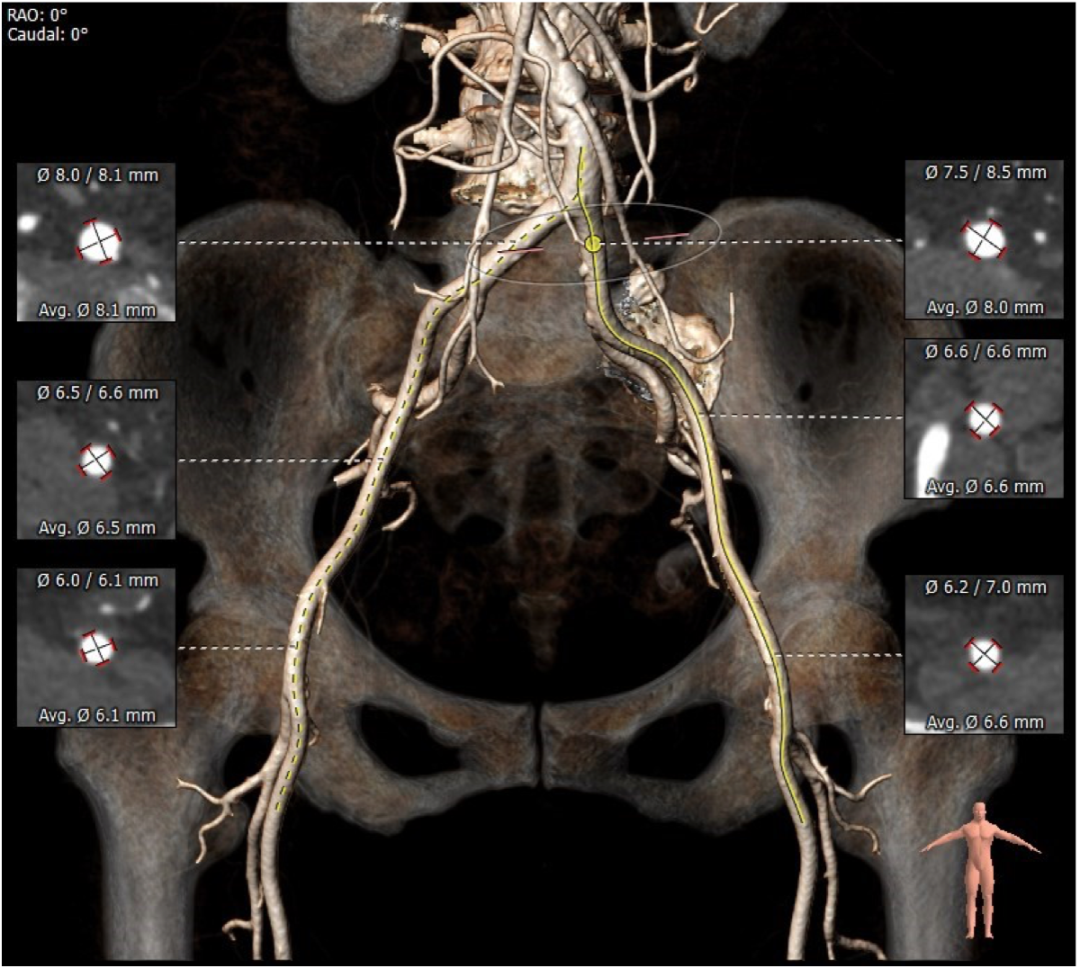

血管外周入路评估

双侧入路血管走形及内径可,整体入路血管条件良好,术中注意轻柔操作。

3.双侧入路血管走形及内径可,整体入路血管条件良好